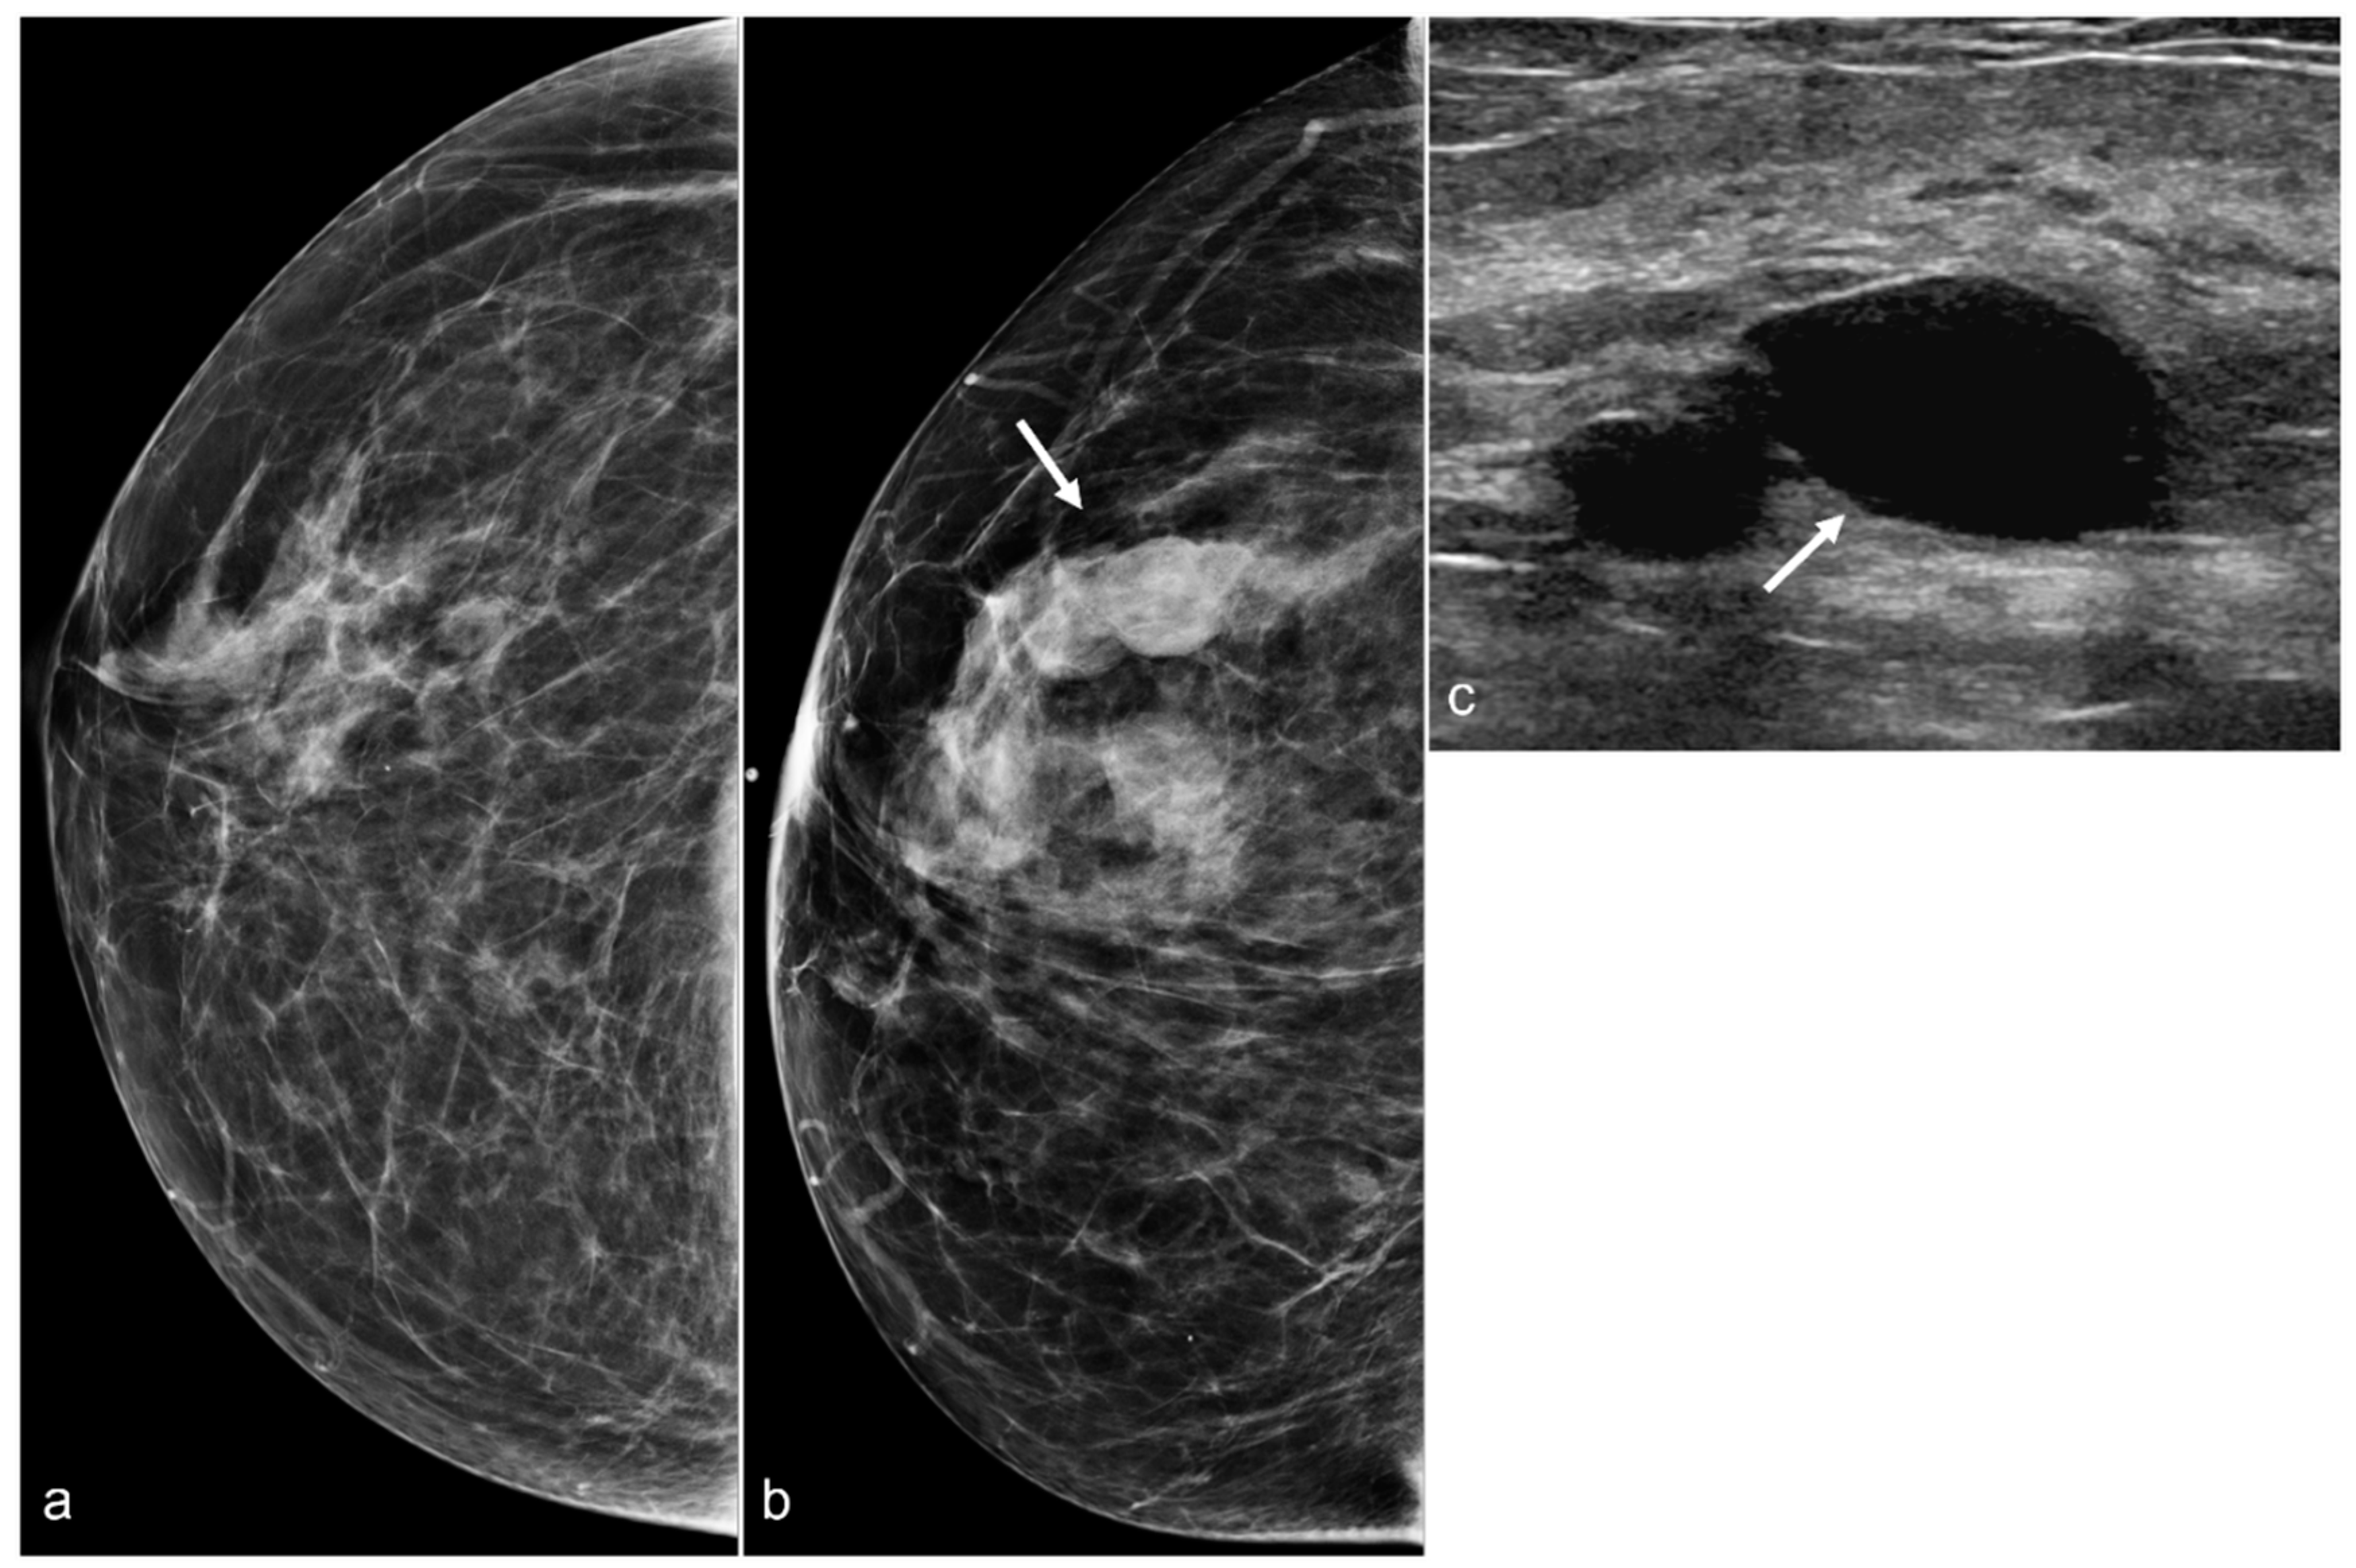

Figure 10. A 58-year-old woman with a history of BIA-ALCL and subsequent BES of retropectoral silicone implants. Post-BES CC mammogram (a) and most recent mammogram CC view (b) demonstrate developing masses (arrow). Right breast ultrasound in the transverse view (c) shows cysts (arrow).